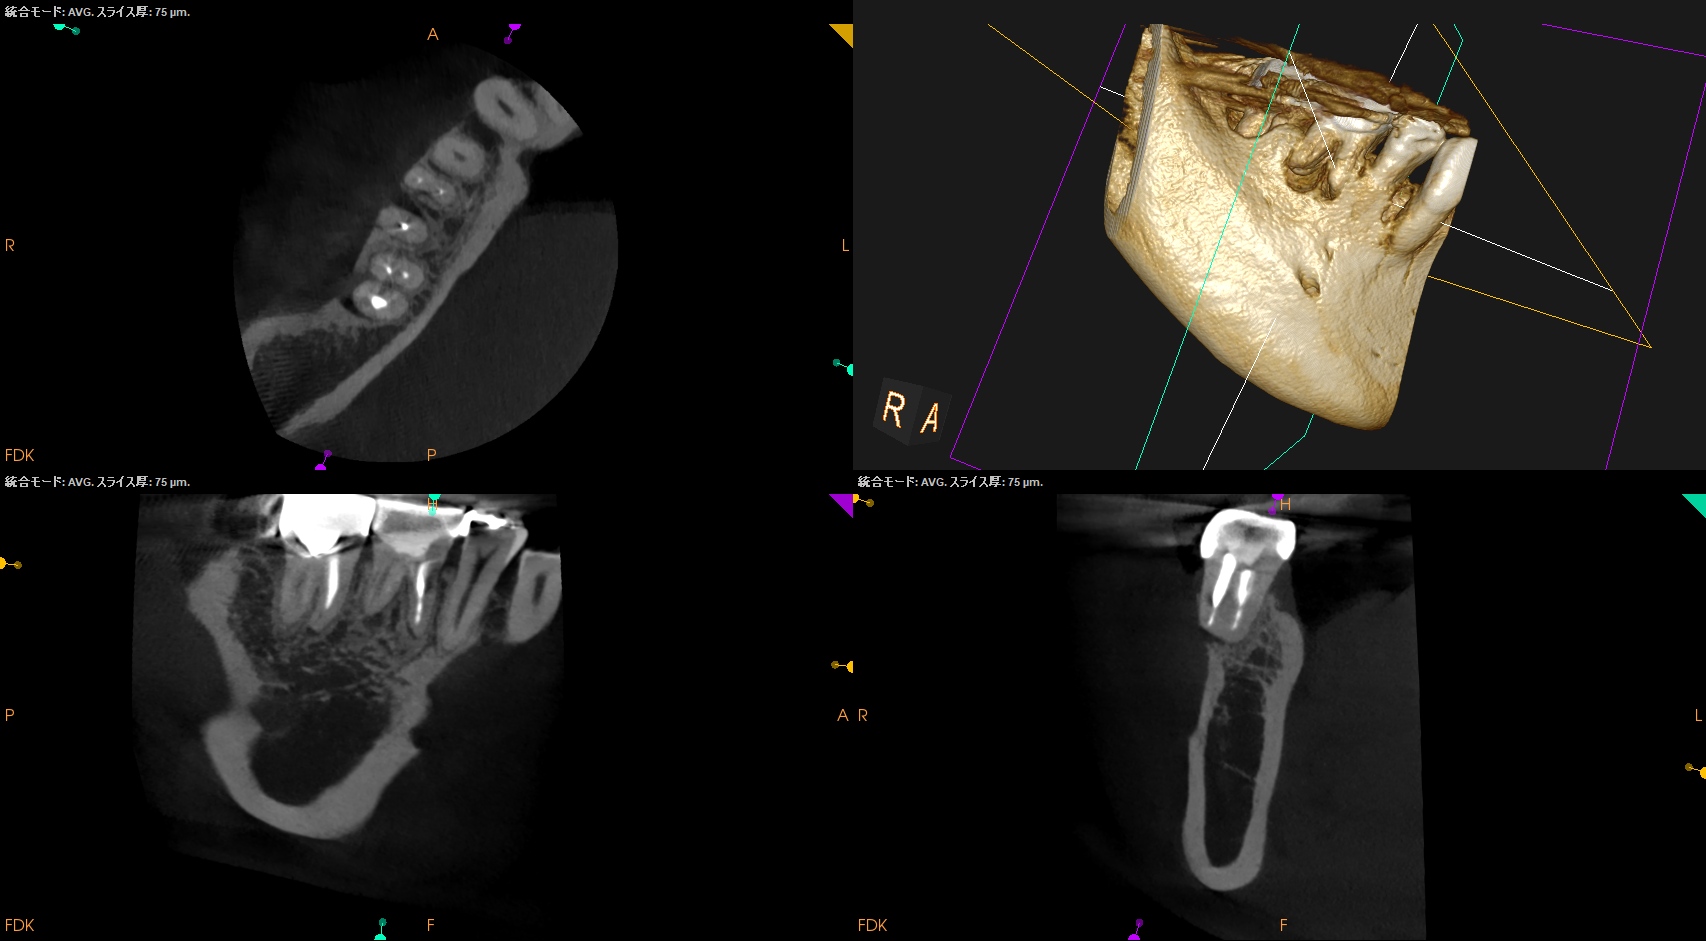

CBCT(2025.9.16)

#30

MB

ML

D

B

頬側の皮質骨が裂開していることが圧痛の原因だろう。

が、Suns tractがないのでApicoectomy!というよりは再根管治療だろう。